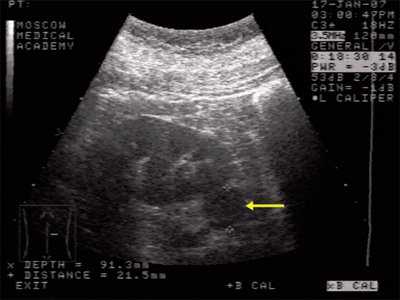

Данные УЗИ: правая почка с четкими неровными контурами, размером 12,5х6,5 см, подвижная при дыхании. Паренхима верхнего сегмента почки толщиной 1,6 см. В нижнем сегменте почки, преимущественно экстраренально определяется округлое образование повышенной эхоструктуры, до 3 см в диаметре. Подвижность почки 2 см.

Левая почка с четкими неровными контурами, размером 11,5х5,5 см. Паренхима однородная, толщиной до 1,7 см. Чашечно-лоханочная система не дилатирована. На границе верхнего и среднего сегментов определяется округлое образование повышенной эхогенности, 1,7 см в диаметре. Подвижность почки - до 2 см (рис. 1).

Рис. 1. Ультрасонограмма - стрелкой указано округлое образование в нижнем сегменте почки.